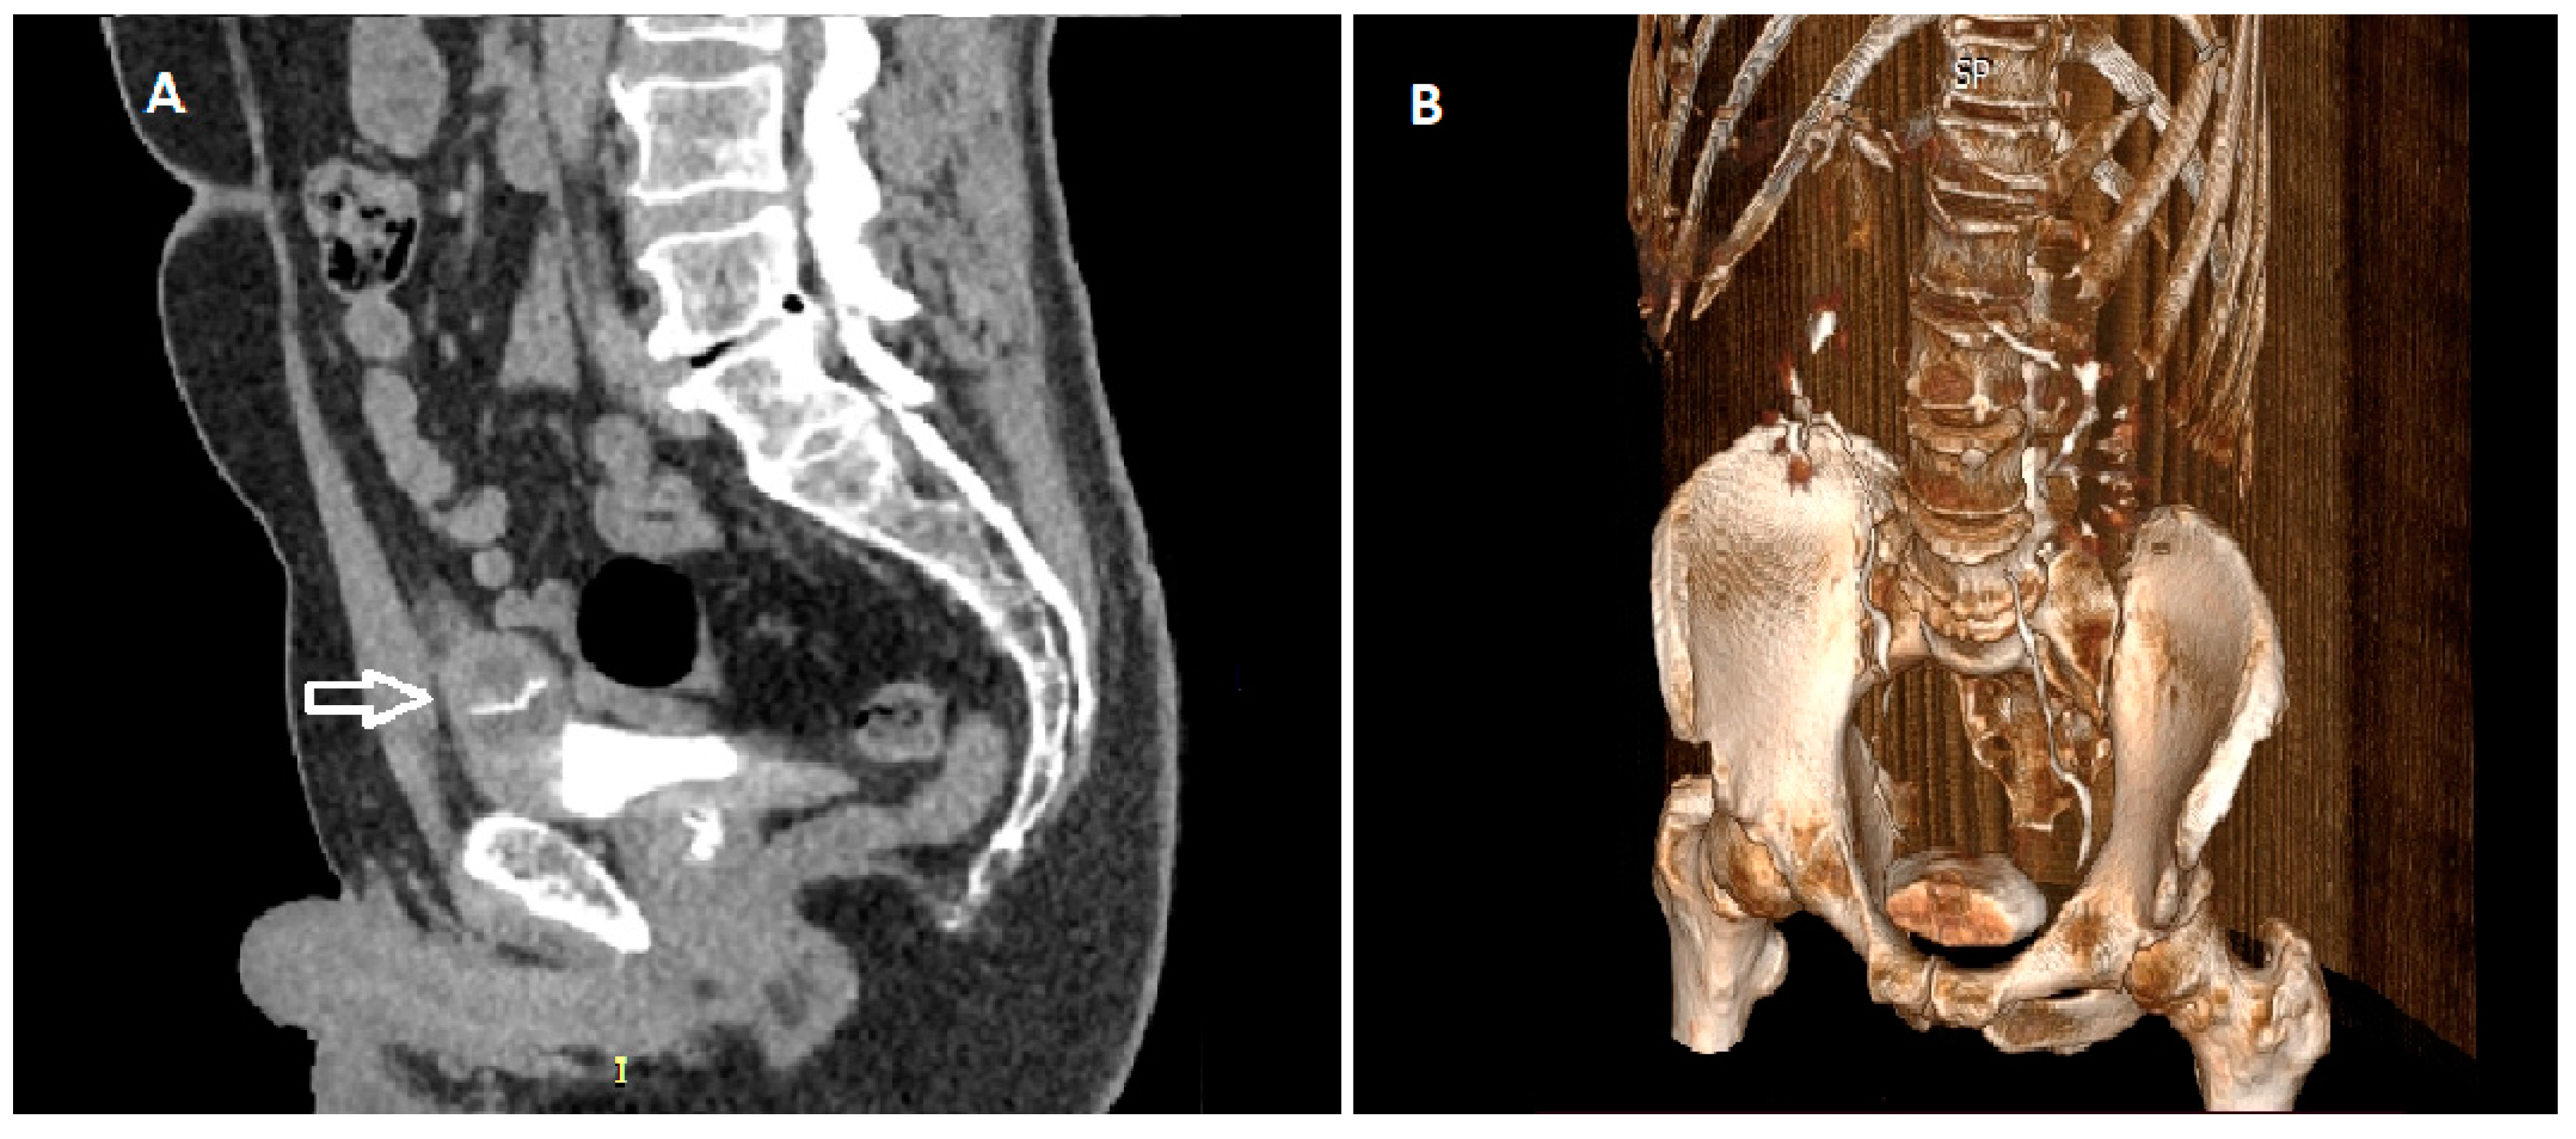

2. Detailed Case Description